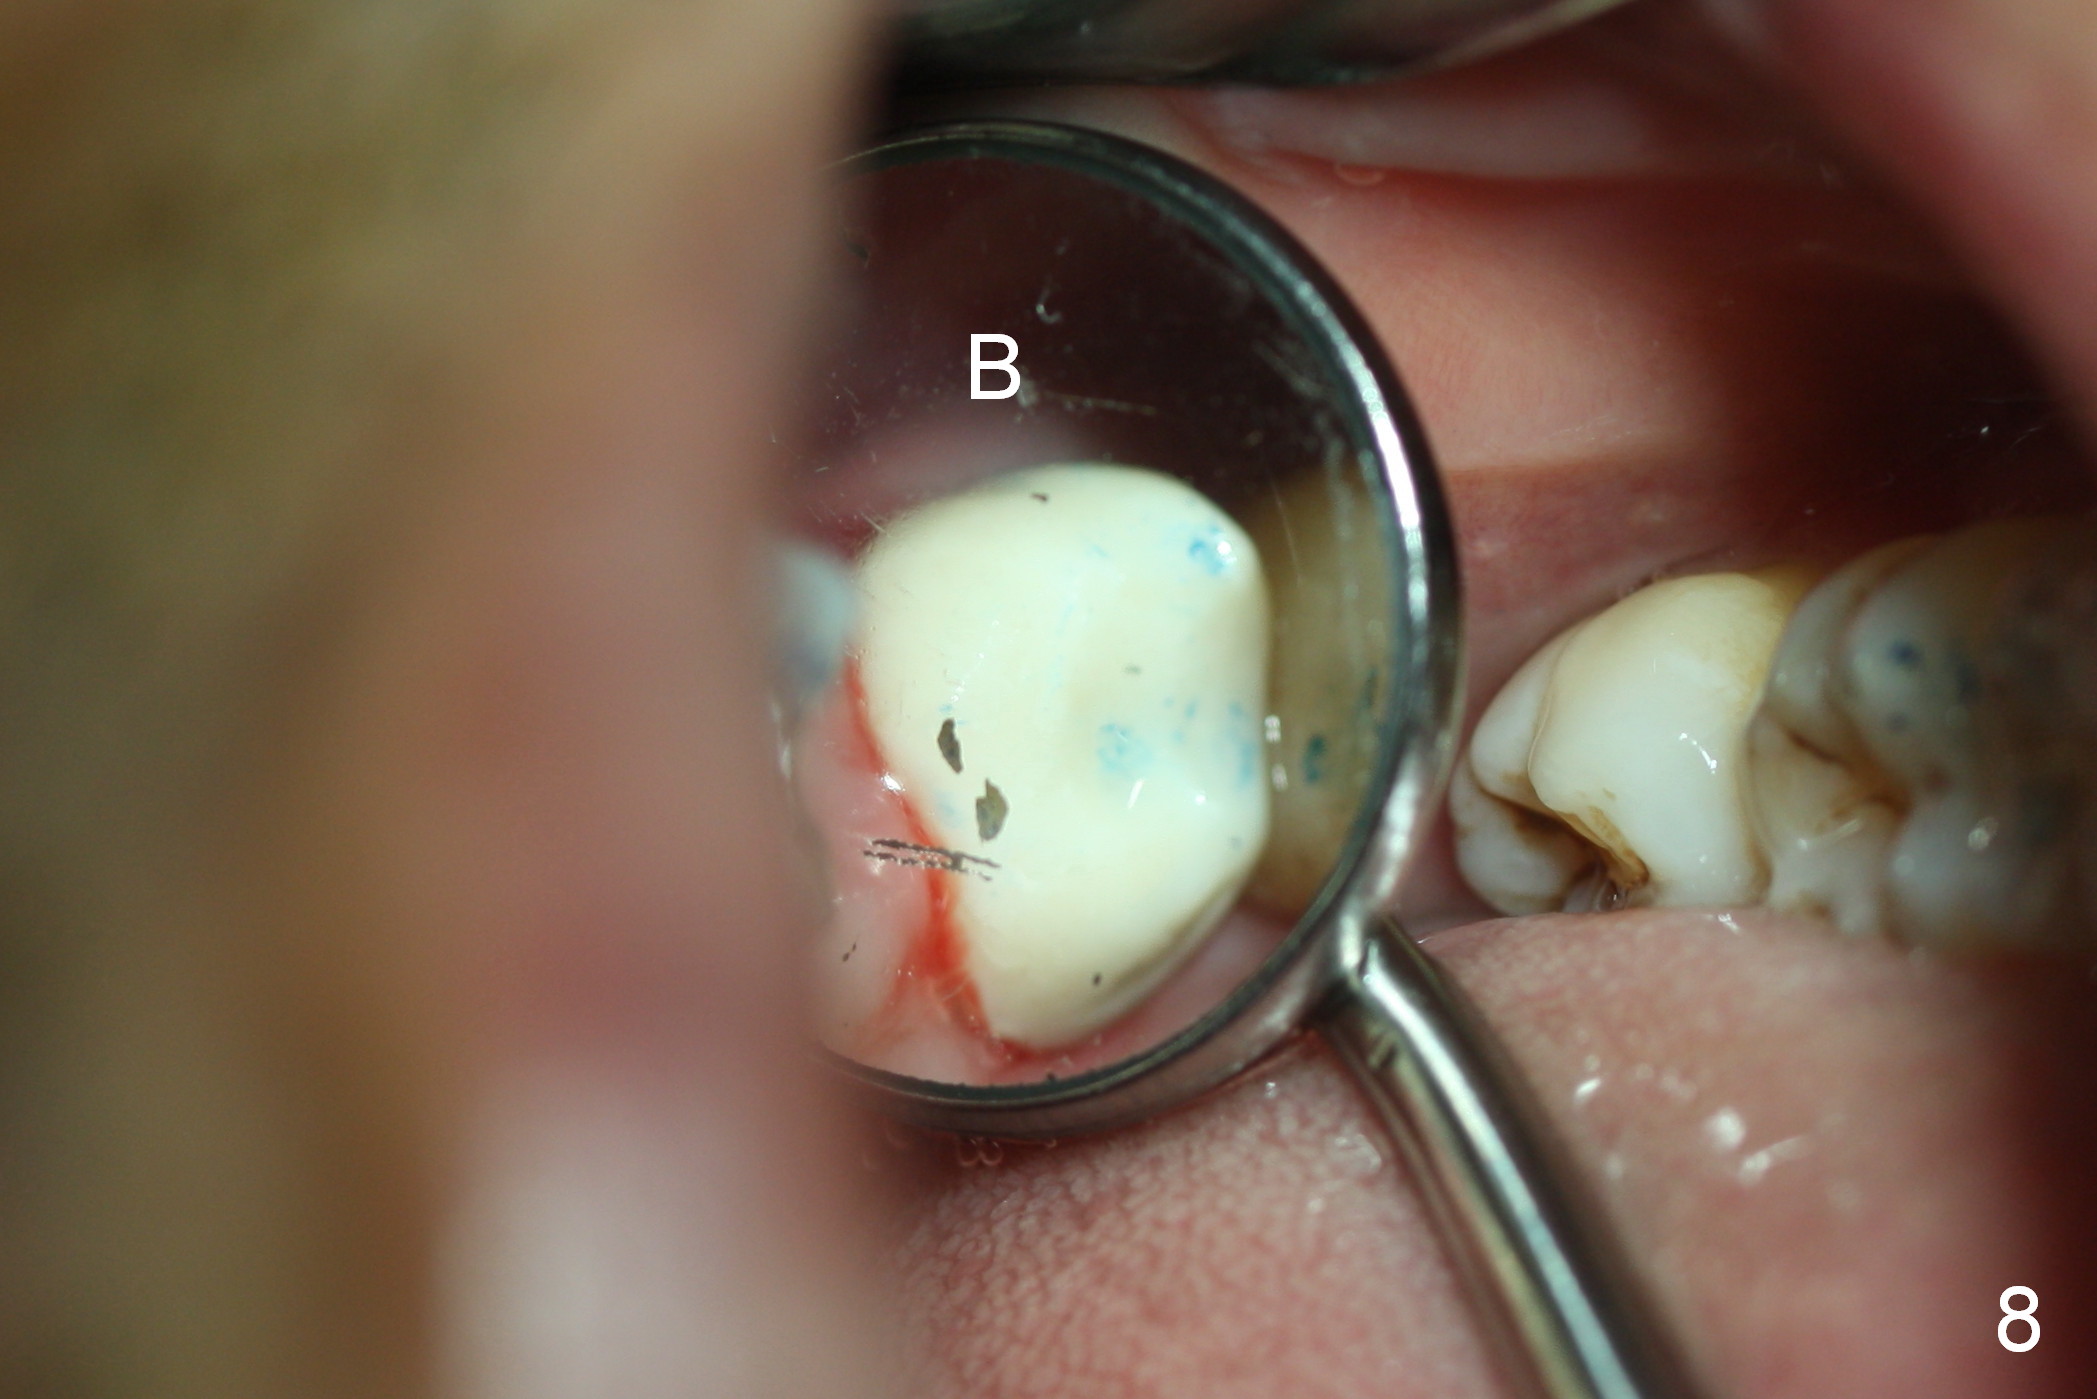

A 50-year-old man (TK) had sign & symptom of crack tooth at #15 (Fig.1) and chose to have root canal therapy done by a specialist. One month later, he returns for crown; exam reveals a crack line mesiodistally (Fig.2). The patient agrees to have immediate implant (Fig.3 design: 6x14 mm). The buccal roots fracture upon luxation. Osteotomy starts in the septum with a 2 mm pilot drill and deviates to the palatal socket, followed by 2, 3, 4 mm tapered osteotomes. A series of taps are placed: 6x17 mm one achieves stability (Fig.4). When the latter is removed, there is no sign of sinus air leakage. A 6x14 mm implant (Fig.5 I) and a 5x3 mm abutment (A) are placed. After abutment height adjustment, an immediate provisional is fabricated. Allograft with Osteogen is placed in the remaining sockets and gaps (Fig.6 *). Fig.7 shows the inner side of the provisional with double arrows indicating the dimension of the abutment, whereas arrowheads the dimension of the socket buccopalatally. When the provisional is cemented (Fig.8 P), it completely seals the socket. As long as the provisional stays, bone graft will not be lost.

The patient returns for follow up 1 week and 1 month postop. The provisional remains in place. It is removed for margin modification 1 month postop: the bone graft having been apparently incorporating into the socket concentrically (from periphery of the socket to the implant) (Fig.9).